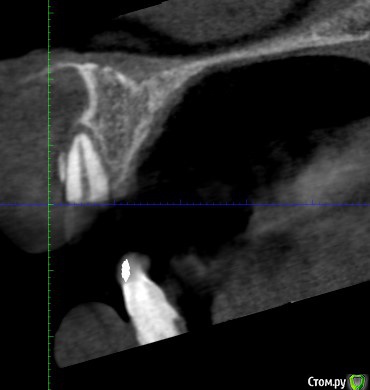

Дмитрий М Опубликовано 29 декабря, 2018 Поделиться Опубликовано 29 декабря, 2018 (изменено) Техник сделает восковой прогноз. И С него сделает шаблон. Больше для подстраховкипокажите пожалуйста фото шаблона и на КТ ширина гребня 9,11мм? срезы корректно выставлены? Изменено 29 декабря, 2018 пользователем Дмитрий М Ссылка на комментарий

bogdan_r Опубликовано 29 декабря, 2018 Автор Поделиться Опубликовано 29 декабря, 2018 (изменено) покажите пожалуйста фото шаблона и на КТ ширина гребня 9,11мм? срезы корректно выставлены?Шаблон будет после нг. Позиция импланта будет немного другая. Ширина в самом узком месте 9.11мм Изменено 29 декабря, 2018 пользователем bogdan_r Ссылка на комментарий